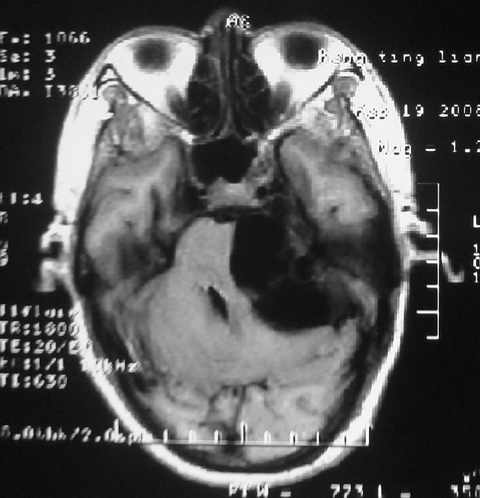

m,72,头疼,头晕两年,伴视力模糊三月,饮食呛咳两天。pe:颈部抵抗,左眼突出,左眼瞳孔约3mm,对光反射消失,双眼失明,伸舌困难,双肺呼吸音粗,心率110次/分,左上肢肌力i级,左下肢屈曲,肌张力高。现有08年2月19mri平扫及10年2月8日mri增强请会诊。ct病灶呈低密度伴散在点、片状等密度区,无明确钙化(无ct片资料可供上传)。[

脑外肿瘤,表皮样囊肿可能性大。

脑外肿瘤,囊实性,环状不规则强化,内听道扩大,考虑神经源性肿瘤

考虑表皮样囊肿。

左侧桥小脑区占位伴梗阻性脑积水----考虑 1神经鞘瘤 2室管膜瘤。

左侧桥小脑区神经鞘瘤伴梗阻性脑积水。

听神经瘤

脑外肿瘤,病灶呈匍匐蔓延,表皮样囊肿可能性大。

脑外肿瘤,病灶呈匍匐蔓延,表皮样囊肿可能性大。支持!

左侧桥脑小脑角区肿瘤并脑积水,考虑听神经瘤,脑膜瘤?

考虑听神经瘤

左侧桥脑小脑角区肿瘤并脑积水,考虑听神经瘤,